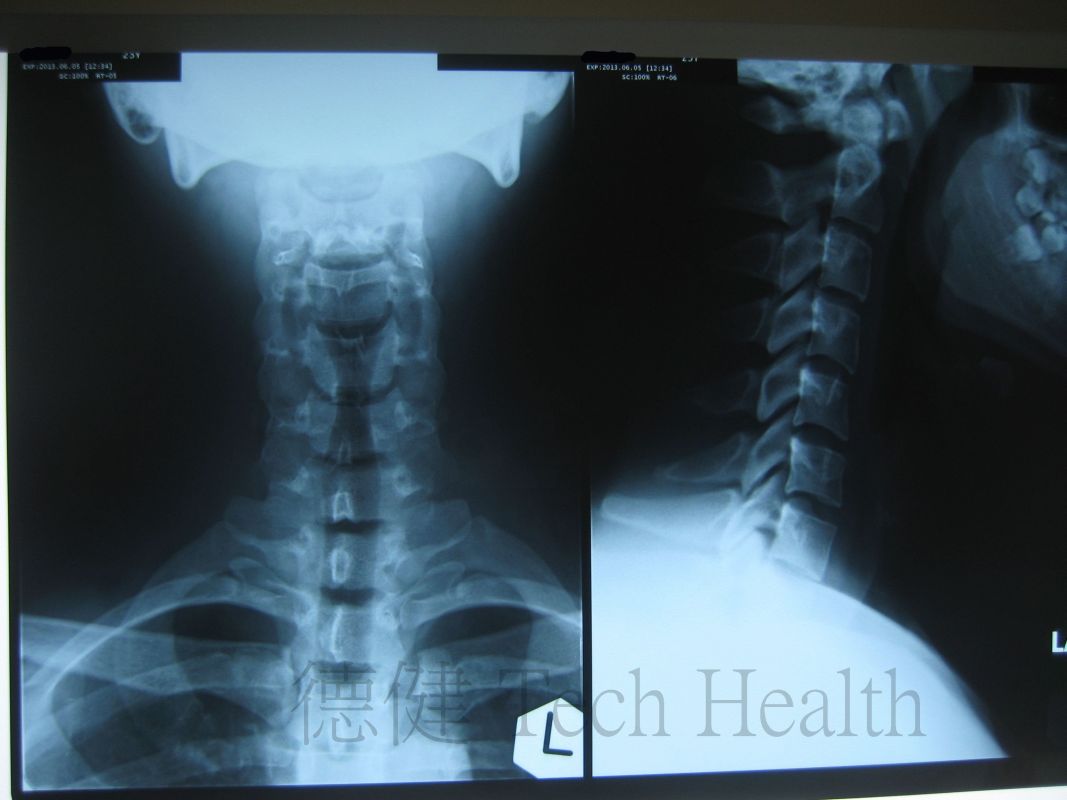

個案一 - 胡先生 23歲 - 肱二頭肌肌腱炎

- 2013-8-2 患者因長期參與投擲動作運動,過度使用肱二頭肌長頭而造成的重複性損傷,造成肌腱及其腱鞘受損與發炎。現見頸背拘緊,右肩關節前方疼痛,疼痛集中於結節間溝,時向遠端放射至肱二頭肌肌腹。腰亦有酸痛不適及肌肉拘緊。